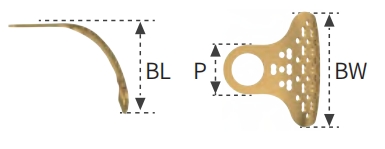

T2 Type

-

Proximal Width: 4 mm

-

Buccal Width (BW): 8 mm

-

Buccal Length (BL): 7 mm

-

Lingual Height: —

-

Thickness: 0.2 mm